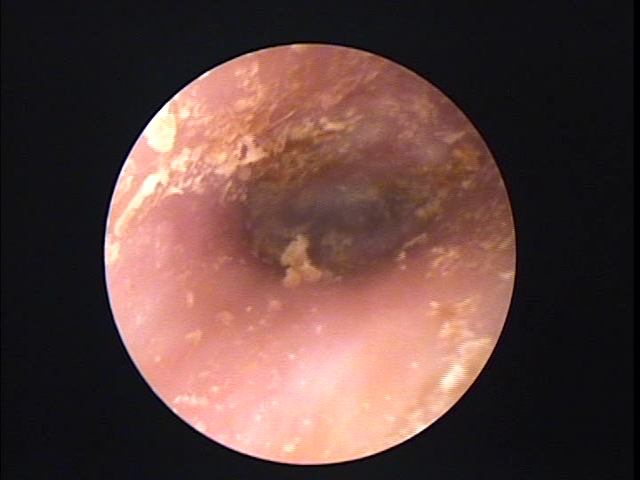

耳について | 千葉耳鼻咽喉科クリニック from chibacl.com